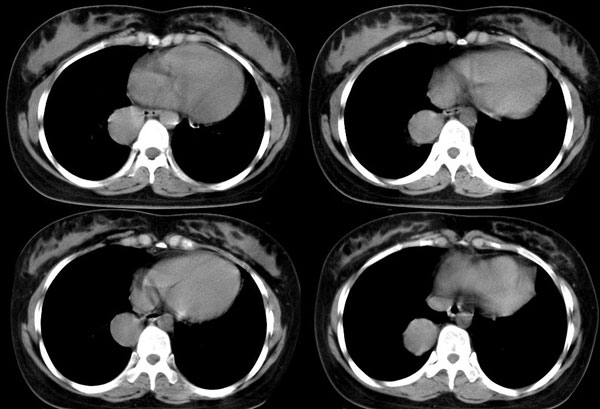

女,22岁,无明显症状

强化

后纵隔食管右侧可见一囊性病灶,密度均匀,边缘光滑,未见钙化,与食管关系密切。无明显强化。

考虑食管囊肿。

首先定位在肺内。肿块最大径在右下肺叶后基底段,胸椎椎体右边偏后部。与气管、食管无关,如果是支气管或食管囊肿应该有细蒂与之连接。肿块边缘光整、密度均匀一致、轻度均匀强化。右主支气管轻度受压,右肺含气量降低,右胸腔略萎陷。

定性:右下肺良性肿瘤。

手术证实 支气管囊肿

自己分析一下误诊的原因,如果不对,请老师们指正:该肿瘤位于支气管分叉处,附着于右主支气管后外壁。因为病灶逐渐长大和重力的关系,呈水滴状下垂,故造成其最大径不在纵隔内的假象。轻度强化也是没有仔细和平扫对比给自己造成的假象。才疏学浅,没有仔细分析病例,也没有仔细体会各位老师的不同意见,草率之至,羞愧!